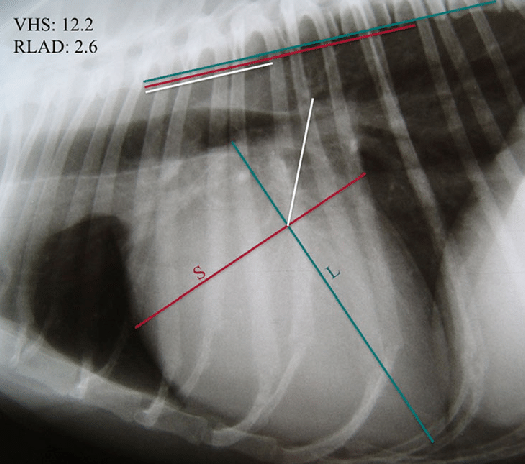

DICOM viewer를 볼때 VHS의 불편함을 줄이기 위해 여러 지표들이 나오고 있는데 이번 소개되는 논문에서는

심장의 장축과 단축을 각각 척추체의 길이로 치환하는게 아니라

두 숫자의 크기를 합하여 척추체 4~8번을 각각 나눴을때 VHS와 어느정도 상관성을 갖는가에 대한 논문이다.

결론의 해석은 개와 고양이의 VHS를 동일하게 사용한다.